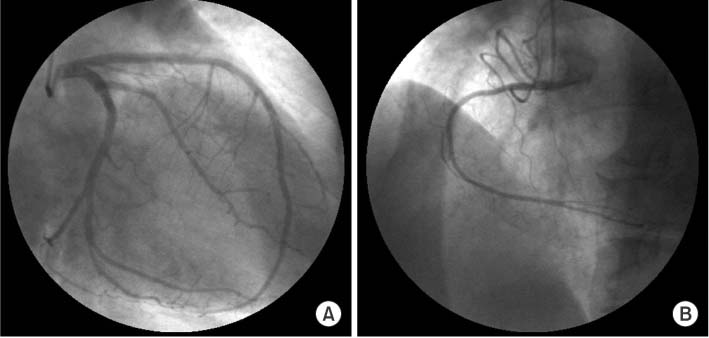

Because the patient complained primarily of nausea and vomiting rather than chest pain, 3% hypertonic saline was administered for hyponatremia until serum sodium level 131 mEq/L, and the symptoms improved following conservative therapy. The patient was maintained on conservative management, including aspirin 100 mg, clopidogrel 75 mg orally. Three days after, cardiac enzyme were significant for CK 190 IU/L, CK-MB 11.25 ng/mL, troponin I 0.83 ng/mL, troponin T 0.065 ng/mL. Seven days after, patient remained stable and cardiac enzymes were decreased (CK 65 IU/L, CK-MB 2.09 ng/mL, troponin I 0.26 ng/mL, troponin T 0.037 ng/mL). On the coronary angiography performed on the seventh day after admission, no significant stenosis was found (

Fig. 3). On the transthoracic two-dimensional echocardiography performed again on the seventh day after admission, improvements were observed in the left ventricular apical dyskinesia that was exhibited previously (

Fig. 3Coronary angiogram. Coronary angiogram shows normal left (A) and right (B) coronary arteries.